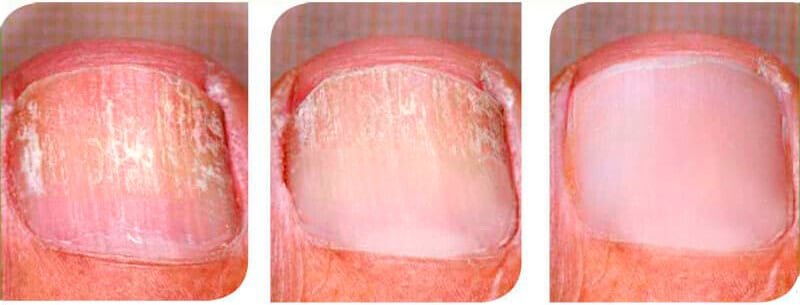

Inicio del tratamientoDos semanas después de comenzar el tratamiento.Cuatro semanas después de iniciar el tratamiento

¡Mira mis resultados!